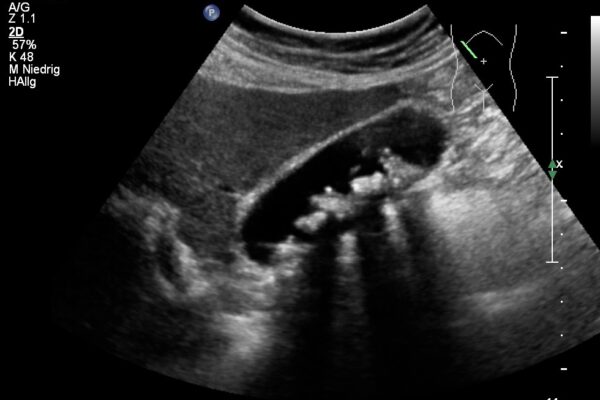

Im Ultraschall der Bauchhöhle beurteilt der Arzt die Grösse, die Struktur und die Lage der Bauchorgane und Gefässe.